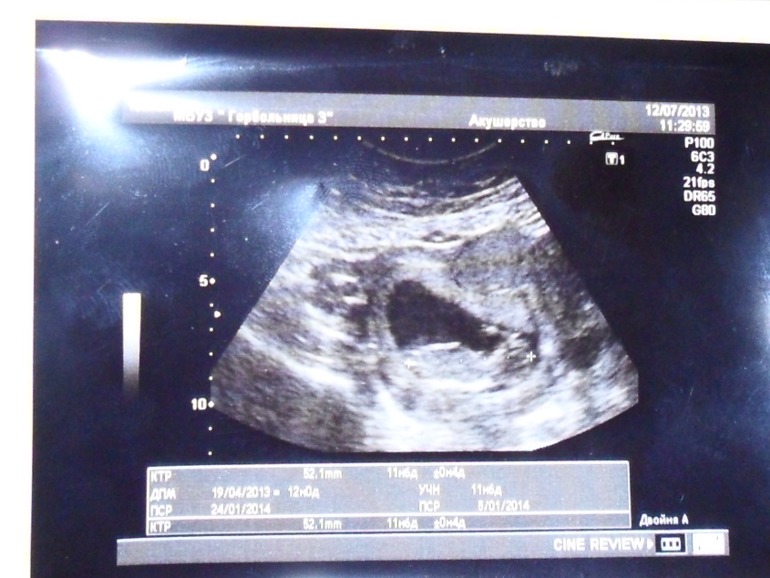

Наконец то я пишу сюда..... сначала хотела подождать до того времени когда нам скажут пол, но не удержалась нам сделали первое фото, дали послушать сердечко, показали наш "сюрприз" -машем руками и ногами, так трогательно я аж прослезилась, вот оно наше чудо